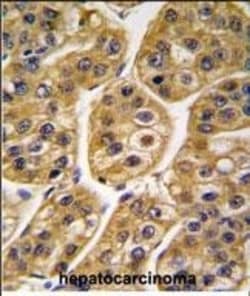

This antibody is predicted to react with bovine and rat based on sequence homology.

| Aplicaciones | Flow Cytometry, Immunohistochemistry (Paraffin), Western Blot, Immunocytochemistry |